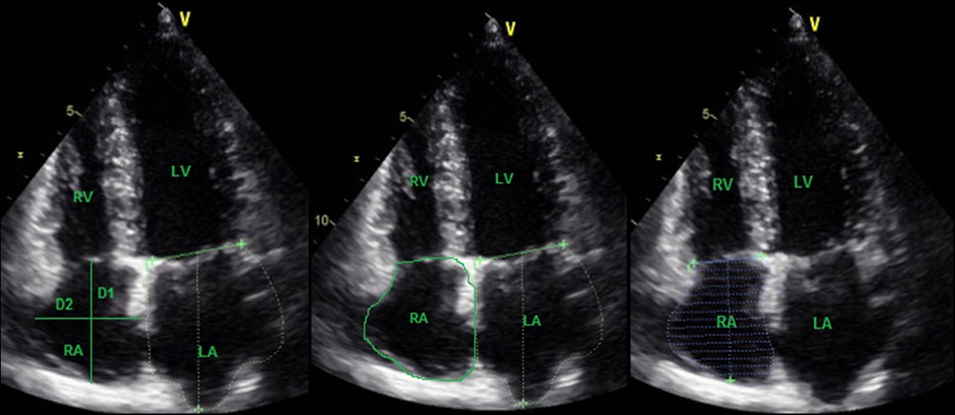

اکوکاردیوگرافی دو بعدی

اکوکاردیوگرافی دو بعدی به صورت استاندارد بوده و یک نمای مخروطی بر روی مانیتور کامپیوتر ایجاد می کند. در این تست حرکت ساختارهای قلب به خوبی مشخص شده و دکتر قلب می تواند ساختارها را به موقع ارزیابی نماید.